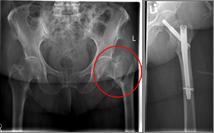

Pertrochanteric fractures, which are not femoral neck fractures close to the hip, are treated with a so-called gamma nail. The rupture here runs through the large and / or small "hillock" (trochanter major and minor) of the thighbone. Here, due to the location of the fracture, the blood supply to the femoral head is NOT compromised. After the operation, an immediate mobilization can take place under pain-adapted full load.

Oberschenkel 5

Picture: In this pertrochanteric femur fracture, a gamma nail was used to stabilize the fracture. The femoral head does not have to be replaced in this case, because the femoral neck is intact and the femoral head is still well supplied with blood.